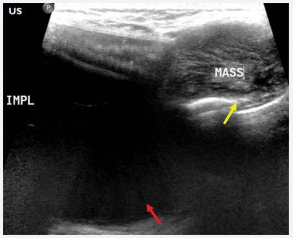

Imaging of implants in the body, including breast implants, facial implants, and buttock implants, is a crucial aspect of evaluating their complications or evidence of failure [3]. Breast implant imaging has been extensively discussed in the literature, with Magnetic Resonance Imaging (MRI) being used to evaluate silicone implant rupture. Facial implants, including cosmetic facial implants and grafts, can also be imaged to assess their expected and complicated outcomes [6]. Additionally, body implants, such as muscular enhancement procedures like silicone arm, calf, and pectoral implants, can be imaged using various modalities. High-resolution ultrasound can be used to screen for breast implant concerns as seen in figure 1 [7].

Implant-associated fibromatosis in a 49-year-old woman with a history of risk-reducing bilateral mastectomy for lobular carcinsoma in situ and silicone implant reconstruction with a palpable mass in the right inframammary region. (a) US image demonstrates a heterogeneously hypoechoic mass (yellow arrow) abutting the implant (red arrow).

Figure 1: Implant-associated fibromatosis in a 49-year-old woman with a history of risk-reducing bilateral mastectomy for lobular carcinsoma in situ and silicone implant reconstruction with a palpable mass in the right inframammary region. (a) US image demonstrates a heterogeneously hypoechoic mass (yellow arrow) abutting the implant (red arrow).